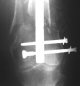

I presented a series of ~25 such cases at EuroTrauma'2004. Many cases were discussed here. I attach am example. Look also recent cases at http://www.hwbf.org/hwb/conf/alex58/scfx.htm,

http://www.hwbf.org/hwb/conf/alex63/alex63.htm

THX, initial images are

1,

2.

At that moment we had in stock only the 10 mm solid nails so of course there was no idea about early weight bearing. But it was quite enough for early knee ROM excersises (see attached). Two locking screws through the distal block provided that.